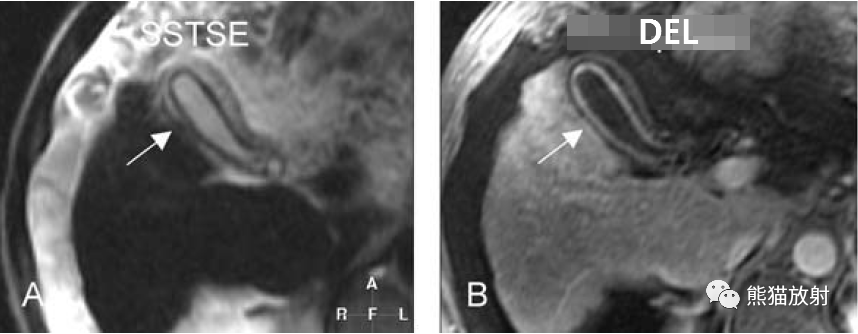

膽囊癌。A~D圖:上方層面,表現(xiàn)如上所述,形成腫物侵及肝臟。E、F圖:下方層面示膽囊壁不規(guī)則增厚,明顯不均質(zhì)強(qiáng)化。

T2壓脂(T2 fatsat):膽囊窩內(nèi)膽囊癌病變較肝臟為高信號(hào),病變頂部向肝內(nèi)擴(kuò)展;

增強(qiáng)動(dòng)脈期(ART):不均質(zhì)強(qiáng)化;

延遲期(DEL):部分廓清,部分持續(xù)強(qiáng)化。